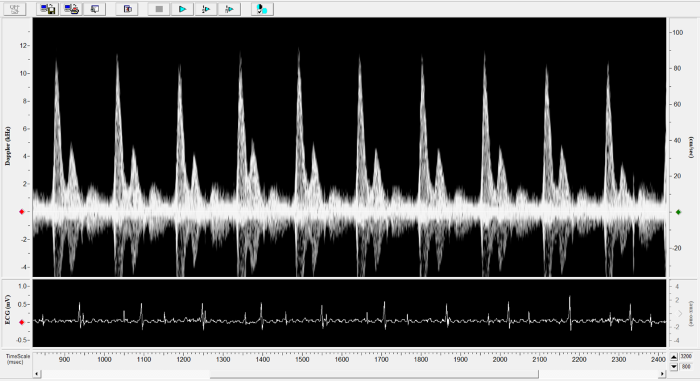

Imaging gallery - Doppler Flow Velocity System

Carotid Image. Image Credit: Scintica Instrumentation Inc.

Renal Flow. Image Credit: Scintica Instrumentation Inc.

Pulmonary Flow. Image Credit: Scintica Instrumentation Inc.

Mouse - Abdominal Aorta. Image Credit: Scintica Instrumentation Inc.

Mouse - TAC Procedure Imaging. Image Credit: Scintica Instrumentation Inc.

Mouse - Coronary Flow Reserve Imaging. Image Credit: Scintica Instrumentation Inc.

Rat - Left Carotid. Image Credit: Scintica Instrumentation Inc.

Rat - Transverse Aorta. Image Credit: Scintica Instrumentation Inc.

Rat - Right Carotid. Image Credit: Scintica Instrumentation Inc.

Rat - Abdominal Aorta. Image Credit: Scintica Instrumentation Inc.

Mouse - Left Anterior Descending Coronary Artery. Image Credit: Scintica Instrumentation Inc.

Mouse - Left Carotid. Image Credit: Scintica Instrumentation Inc.

Mouse - Mitral Inflow. Image Credit: Scintica Instrumentation Inc.

Mouse - Ascending Aorta. Image Credit: Scintica Instrumentation Inc.